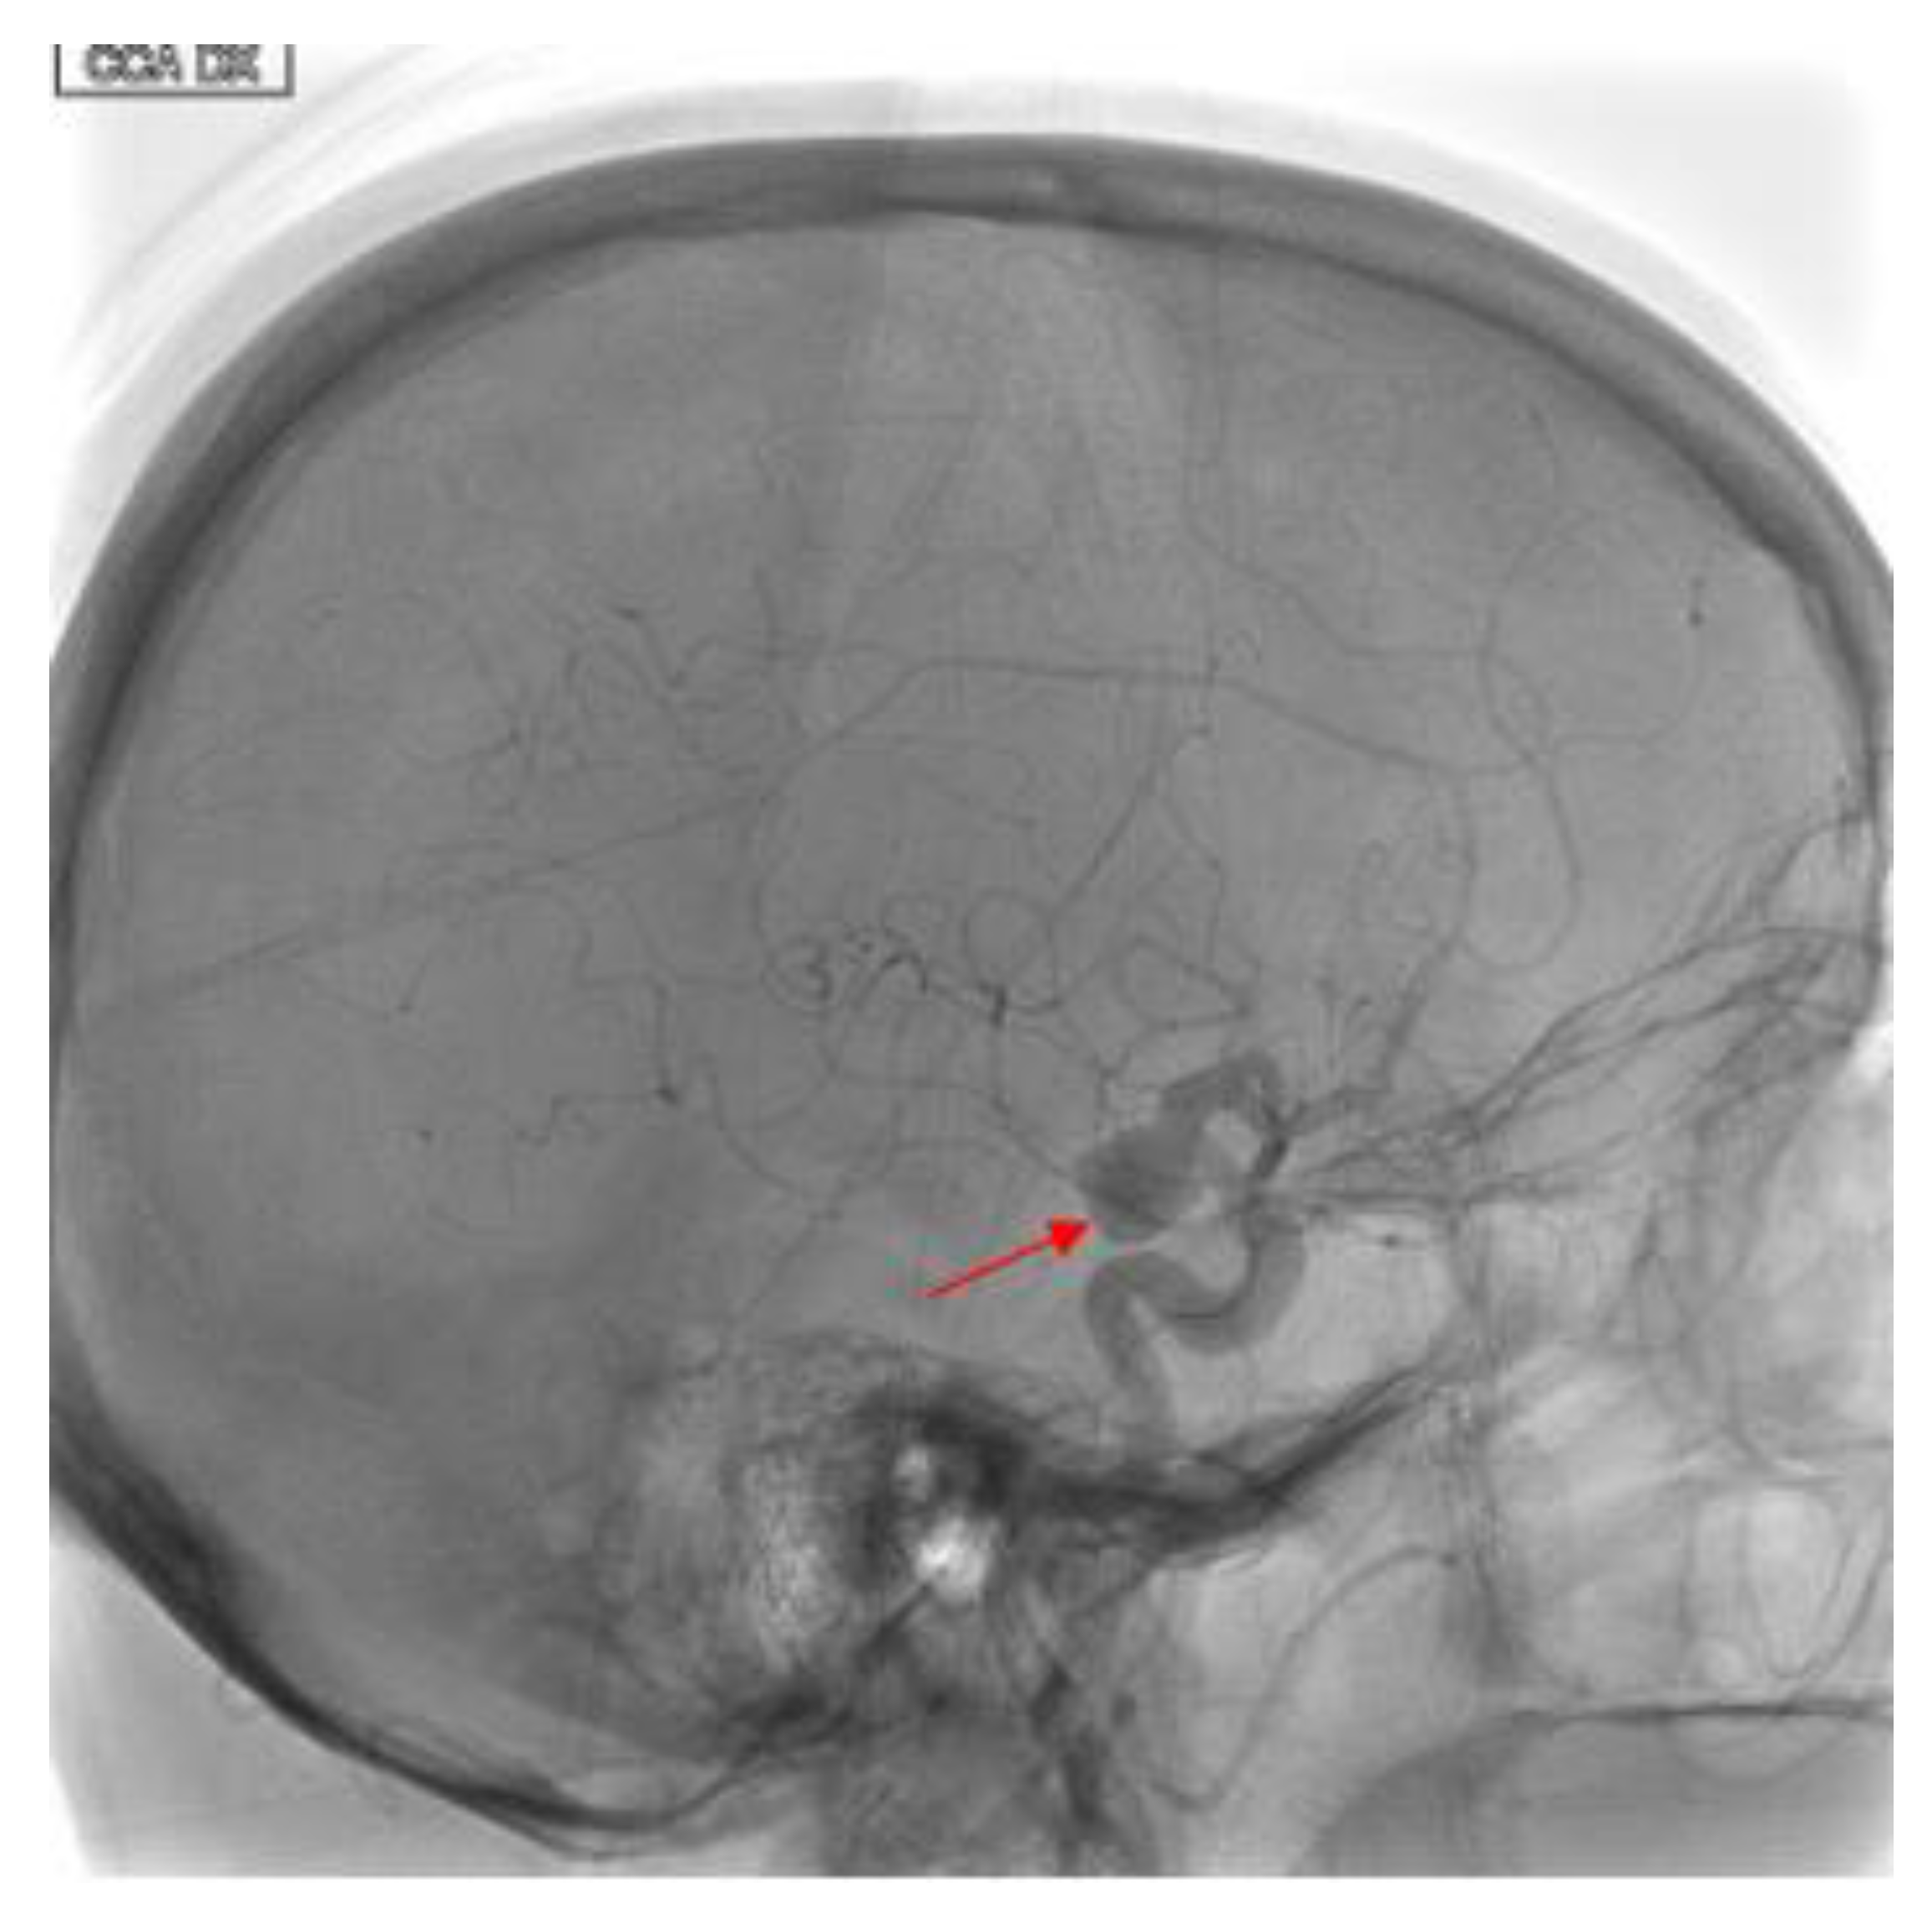

2. Case Presentation